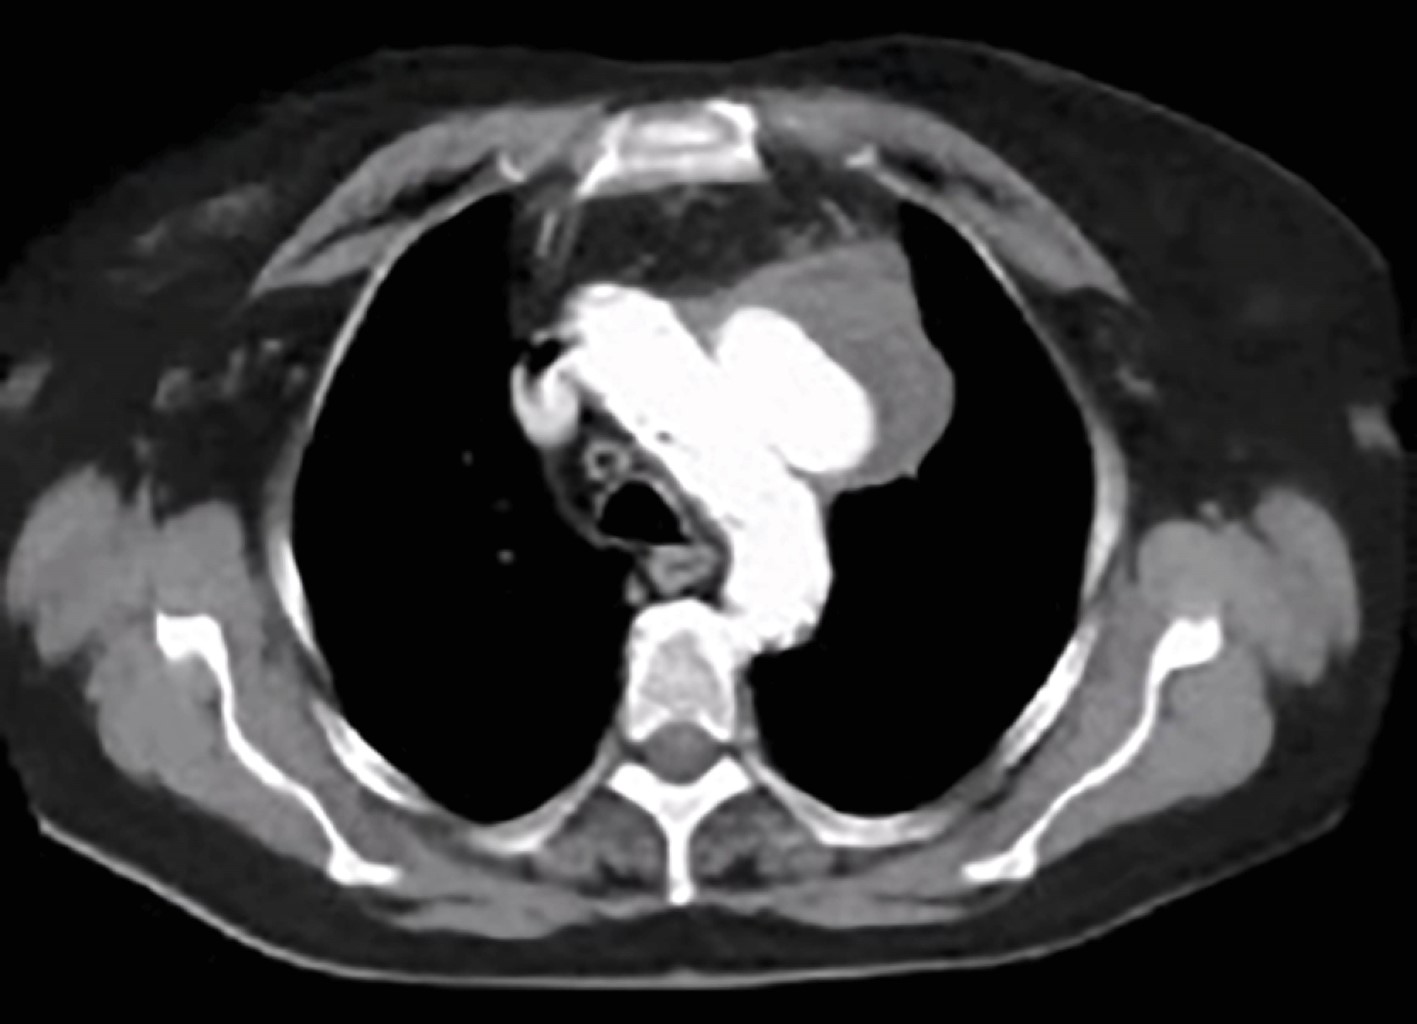

Figura 3